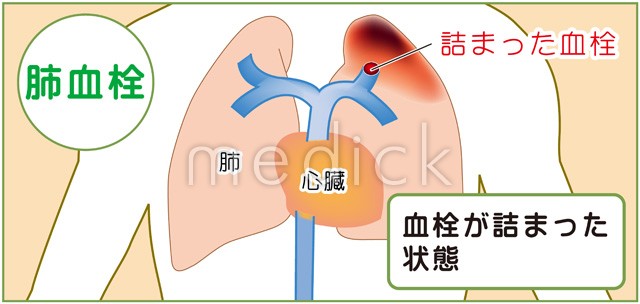

肺血栓症のイラスト - 医療のイラスト・写真・動画、素材販売サイトのメディック medick。

肺血栓塞栓症のベクター画像イラスト。血管血栓症」のベクター画像素材 ロイヤリティフリー737751463Shutterstock。

慢性血栓塞栓性肺高血圧症千葉大学大学院医学研究院 呼吸器内科学。